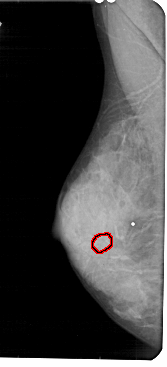

A_1837_1.LEFT_MLO

FILE: A_1837_1.LEFT_MLO.OVERLAY

TOTAL_ABNORMALITIES 1

ABNORMALITY 1

LESION_TYPE CALCIFICATION TYPE ROUND_AND_REGULAR DISTRIBUTION CLUSTERED

ASSESSMENT 4

SUBTLETY 3

PATHOLOGY BENIGN

TOTAL_OUTLINES 1

BOUNDARY